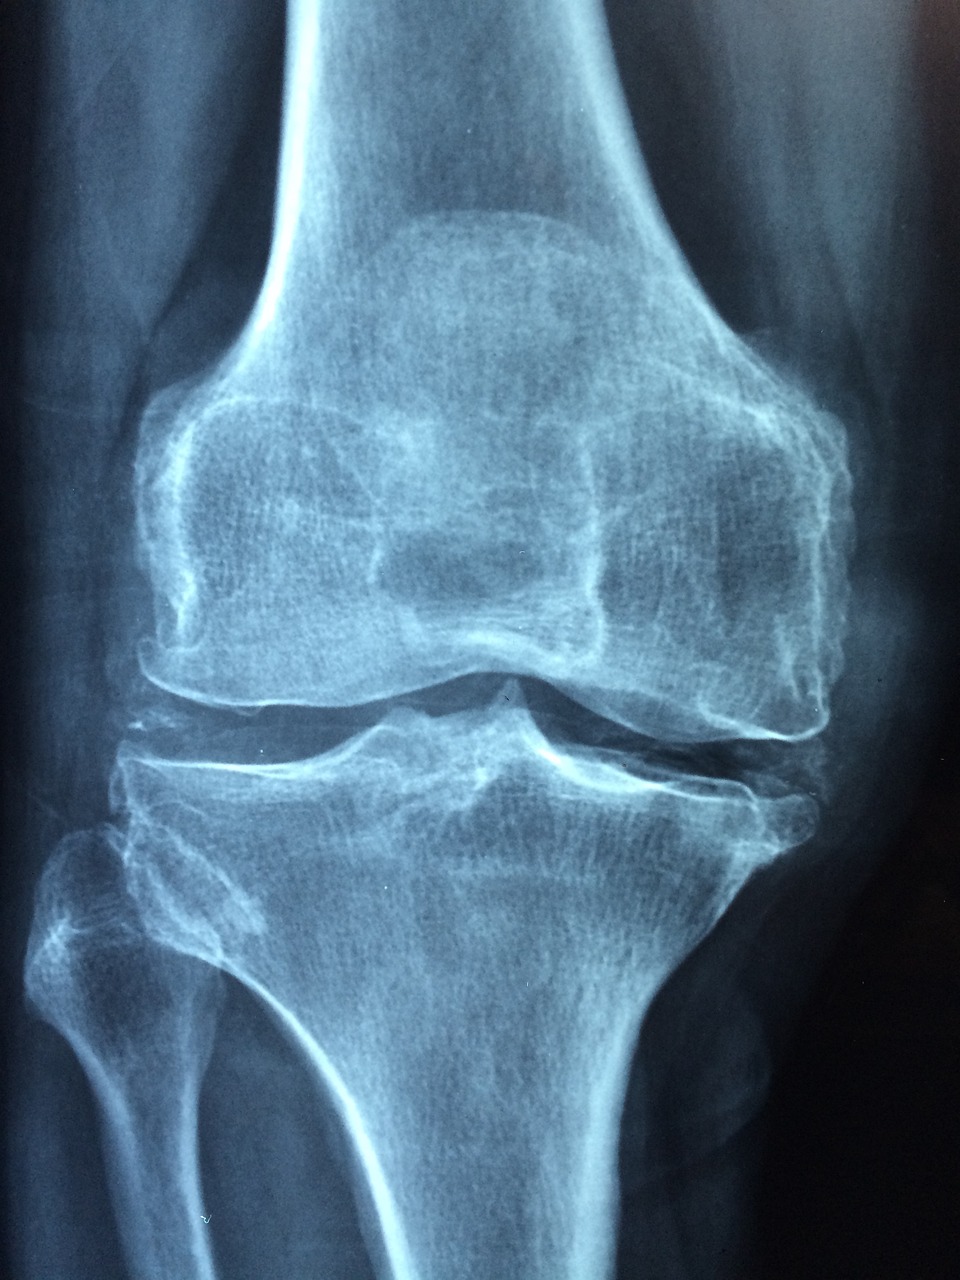

- 4. 수술: 심한 경우, 손상된 관절을 수술로 치료하거나 교체할 수 있습니다.